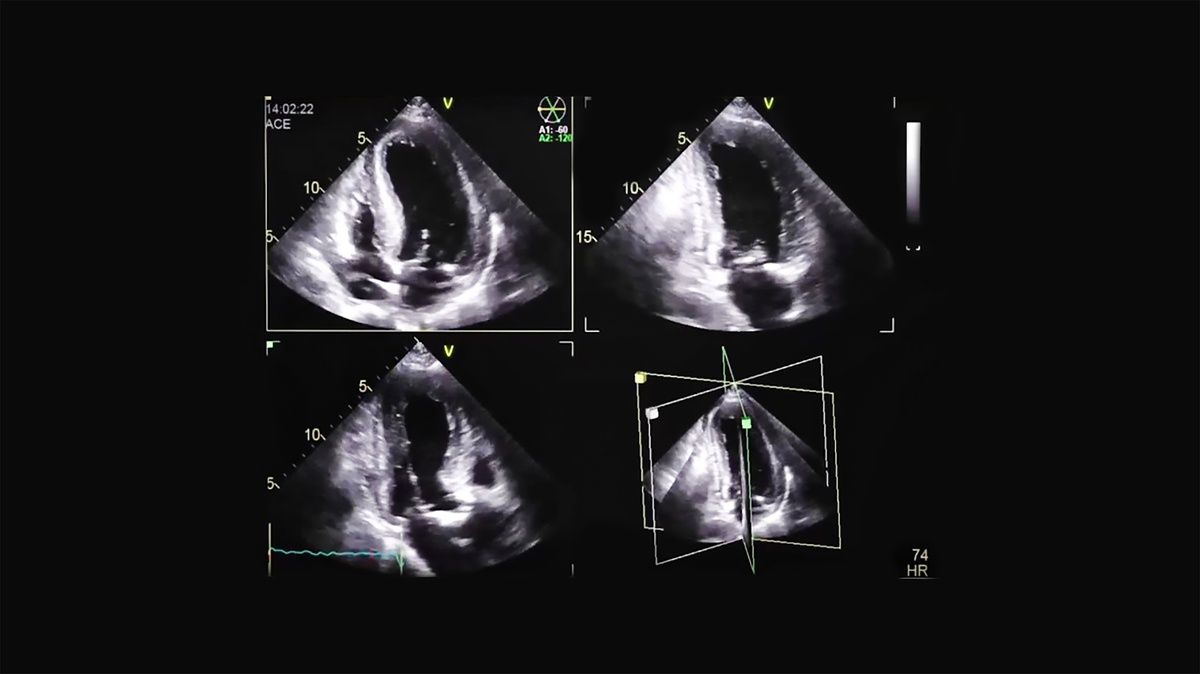

Pacjent z wysiłkowymi bólami w klatce piersiowej i głośnym szmerem wyrzutowym

Złożona wada aortalna – ciężka stenoza i umiarkowana niedomykalność

Echokardiografia przezklatkowa

Ocena przerostu mięśnia lewej komory

Ocena zwężenia i niedomykalności zastawki aortalnej

Ocena globalnej funkcji lewej i prawej komory